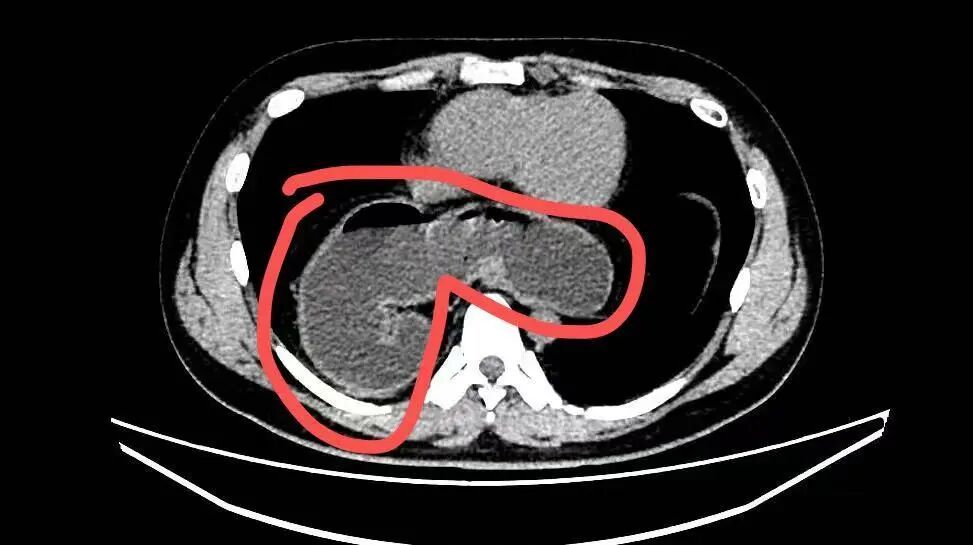

直到去年10月,因为反复咳嗽不止并出现迁延不愈的肺炎,林先生在当地医院就诊,肺部CT检查中发现:一部分的胃竟然“跑”进了胸腔里!

影像资料显示,小伙子的部分胃通过食管裂孔疝“逃跑”至胸腔。